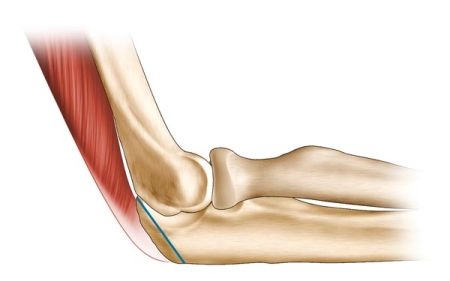

Forage Résection Osseux Percutané (FROP) pour traiter l’ostéome ostéoïde : Technique, trucs et astuces